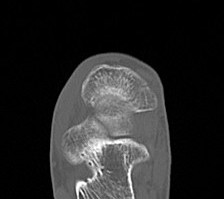

Imaging

Acute displaced navicular fracture